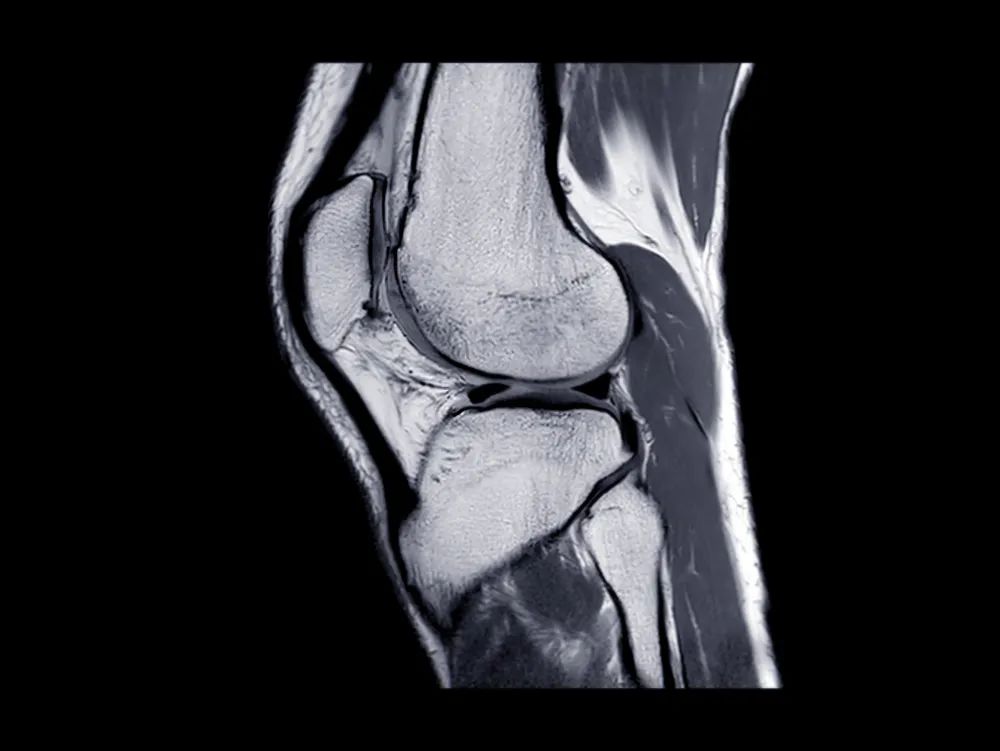

图源:站酷海洛

对于骨折不愈合、畸形愈合所致的关节面不平整以及髌股关节对应关系不良可采用 CT 检查。MRI 有助于诊断软骨缺损和损伤。